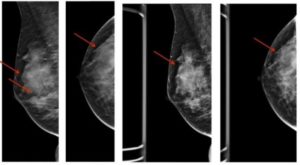

После первичного обследования по показаниям или с профилактической целью врач-маммолог назначит следующие исследования:

- маммография (после 35 лет при подозрении на фиброзную патологию проводить ультразвуковое исследование не информативно);

При обнаружении узловой или кистозной формы ФКМ обязательным этапом обследования является проведение пункционной биопсии под контролем УЗИ, которое поможет исключить пролиферативные и предраковые процессы в груди.

Как показывают отзывы врачей, с помощью УЗИ можно диагностировать узловые и кистозные формы заболевания. Для выявления фиброза лучше использовать маммографию.